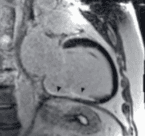

Working with MIRACL.ai means partnering with a leading academic Core Lab in multimodal cardiovascular imaging, at the heart of a clinical, scientific and technological environment of excellence.

MIRACL.ai supports you throughout the lifecycle of your projects, from data to scientific valorization, according to recognized methodological, regulatory and academic standards.

Expert and standardized centralized review

Image analysis by specialized readers following validated protocols, with divergence management, traceability and quality control.

Producing reliable ground truths

Annotations, segmentations, scorings and imaging variable extractions used as references for clinical research and algorithm development.